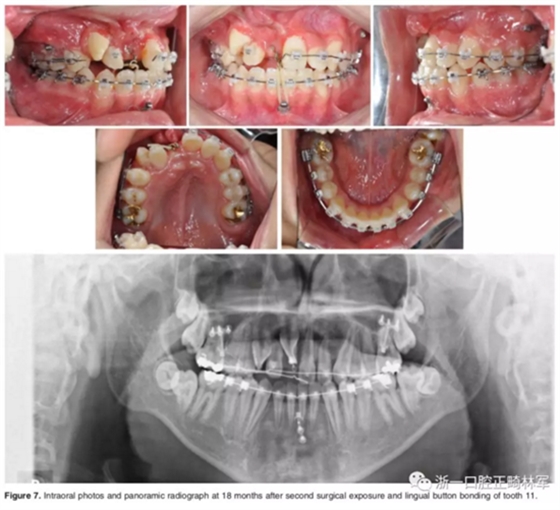

二期手術(shù)主要是牽引中切牙:于上頜前牙區(qū)腭側(cè)作切口,翻全厚瓣,在切牙唇側(cè)粘扣掛結(jié)扎絲牽引;軟組織愈合后,牽引開始。為施加合適的垂直向力,在下頜前牙區(qū)放置C型管,掛橡皮筋牽引。14個(gè)月后,切牙牙冠萌出。使用mini管代替托槽,對切牙、尖牙進(jìn)行矯治;矯治過程采用輕力,0.014-in鎳鈦絲。

第三階段:

中切牙旋轉(zhuǎn)矯正后,患者至牙周科醫(yī)生處行右上前牙區(qū)骨增量手術(shù)。前牙區(qū)翻瓣后,使用Bio-oss及膠原膜覆蓋所有骨壁開窗或較薄處,皮瓣復(fù)位縫合。2周后,繼續(xù)進(jìn)行正畸矯治。